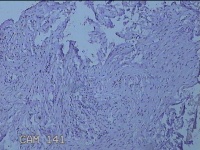

右输卵管囊肿

性别

女

年龄

23岁

临床诊断

左输卵管积水 慢性盆腔炎 盆腔子宫内膜异位症

一般病史

发现右输卵管积水

标本名称

左输卵管囊肿

大体所见

灰白暗红色囊壁样组织2.8x2x0.3cm一堆,表面光滑,因已切开,囊内容物已流失,囊壁厚0.1cm。